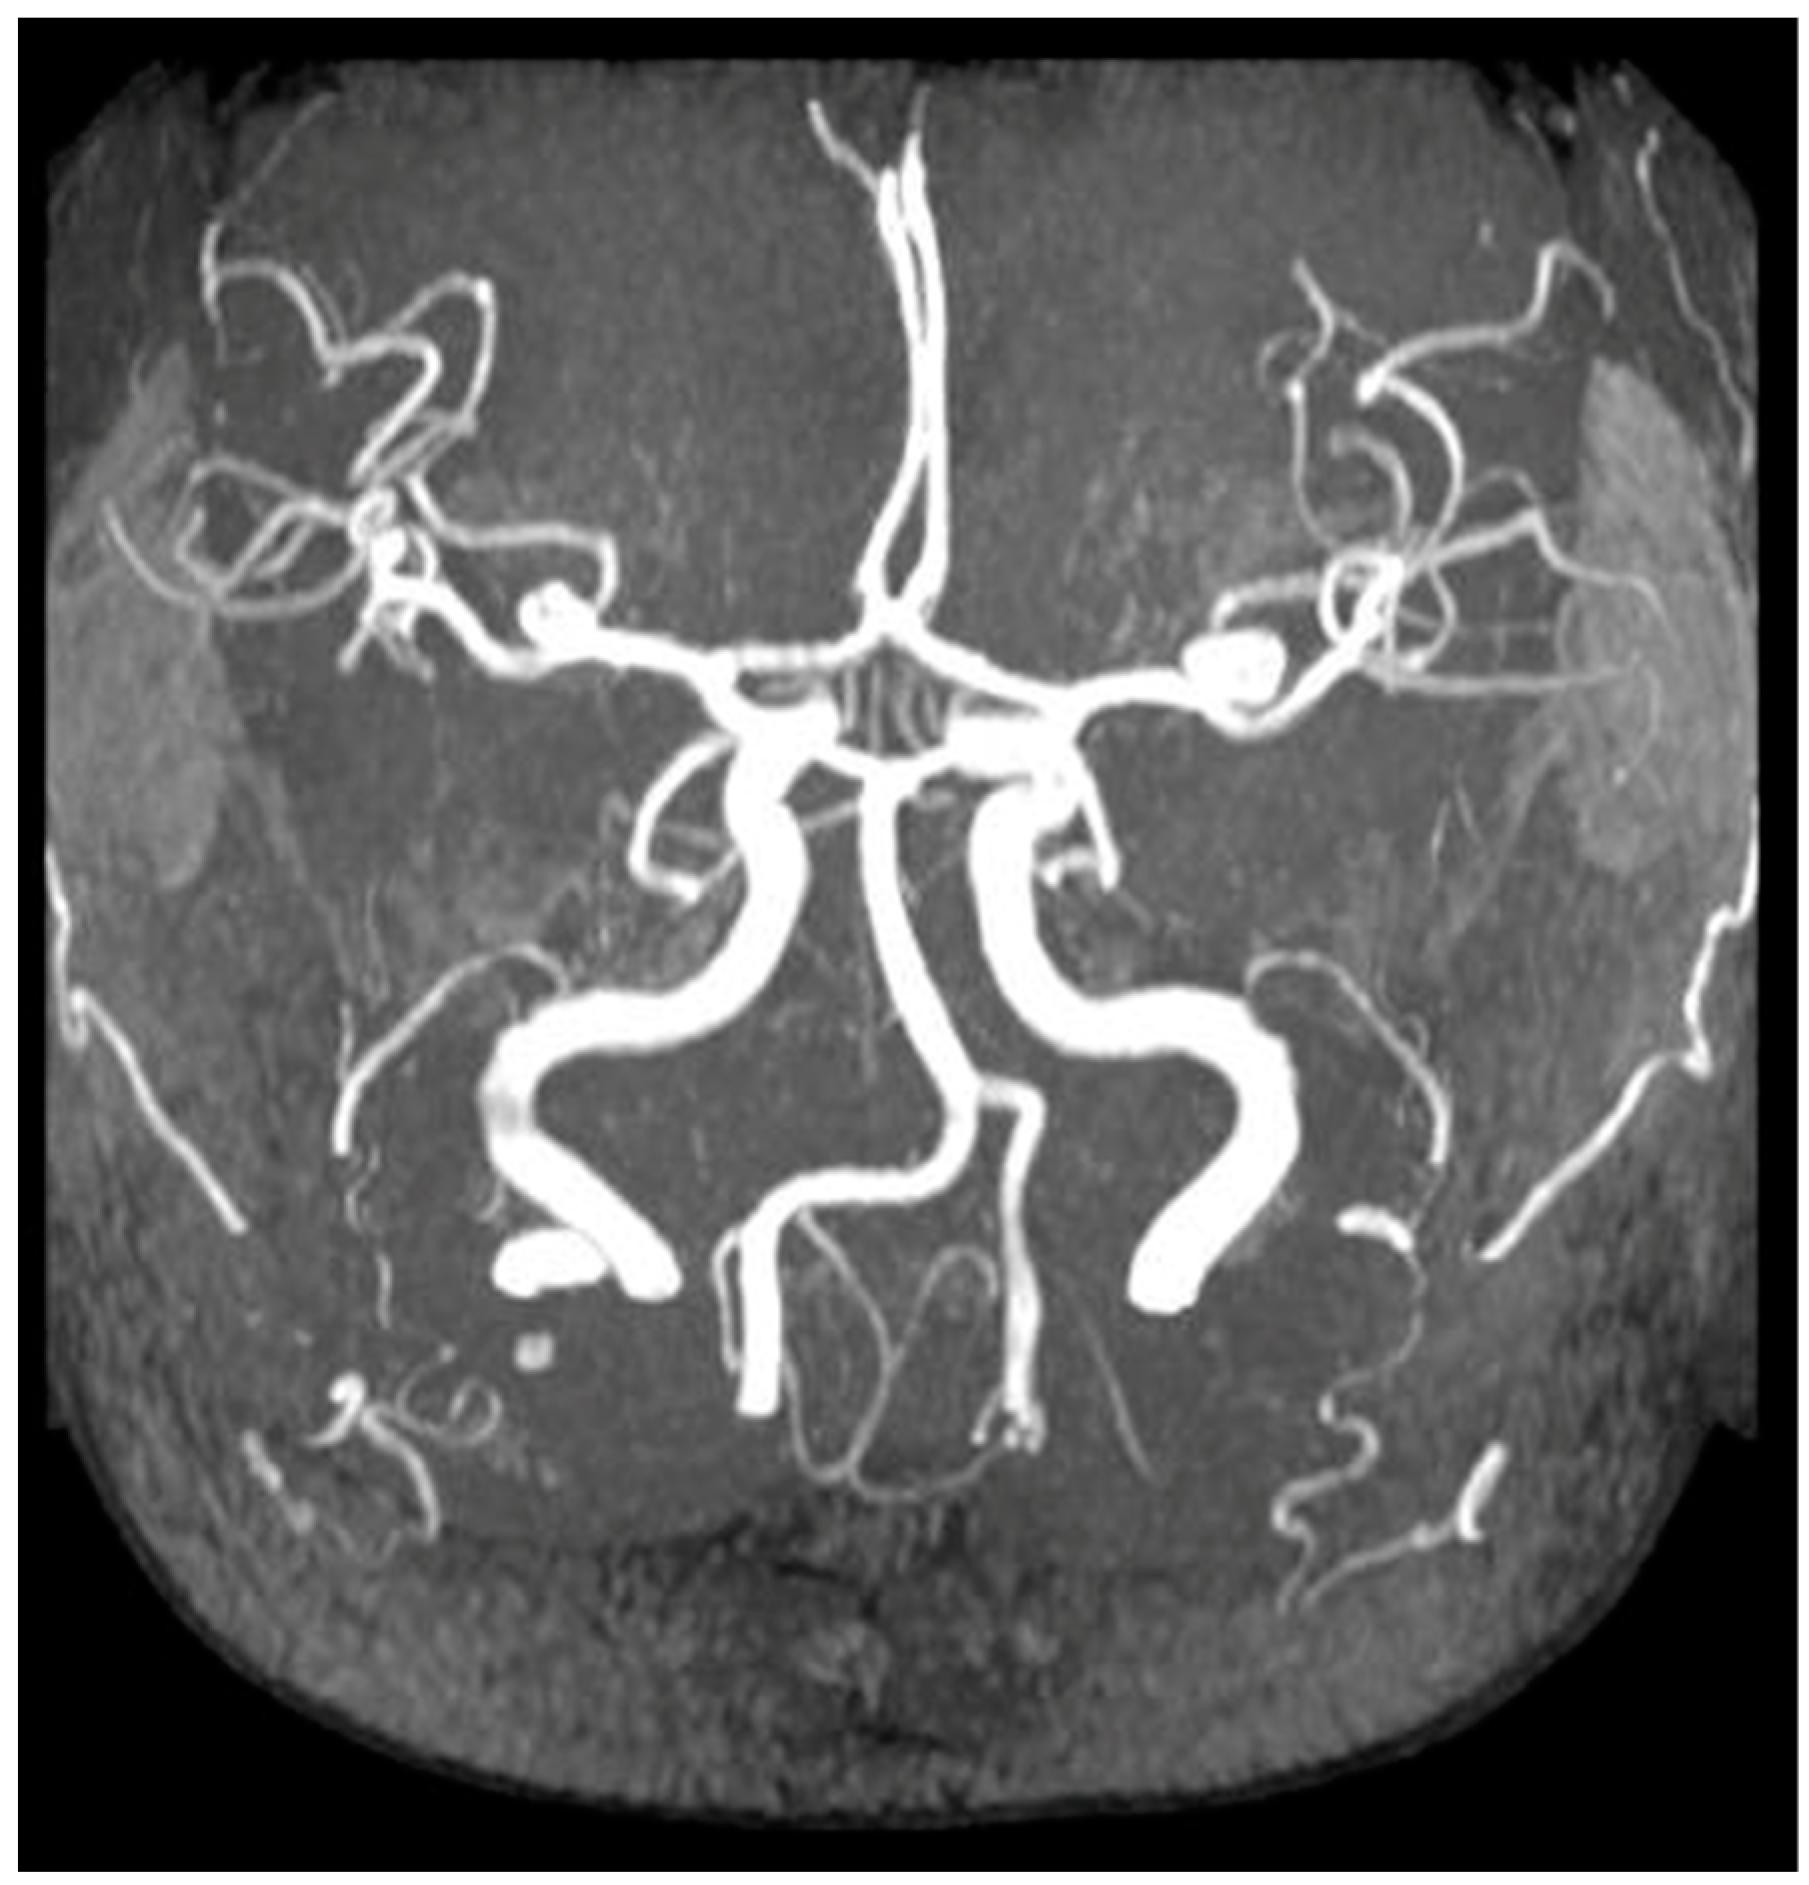

- Sanchis, I.M.; Shukoor, S.; Irazabal, M.V.; Madsen, C.D.; Chebib, F.T.; Hogan, M.C.; El-Zoghby, Z.; Harris, P.C.; Huston, J.; Brown, R.D.; et al. Presymptomatic Screening for Intracranial Aneurysms in Patients with Autosomal Dominant Polycystic Kidney Disease. Clin. J. Am. Soc. Nephrol. 2019, 14, 1151–1160. [Google Scholar] [CrossRef] [PubMed]

- Zhou, Z.; Xu, Y.; Delcourt, C.; Shan, J.; Li, Q.; Xu, J.; Hackett, M.L. Is Regular Screening for Intracranial Aneurysm Necessary in Patients with Autosomal Dominant Polycystic Kidney Disease? System. Rev. Meta Anal. Cerebrovasc. Dis. 2017, 44, 75–82. [Google Scholar] [CrossRef] [PubMed]

- Haemmerli, J.; Morel, S.; Georges, M.; Haidar, F.; Chebib, F.T.; Morita, A.; Nozaki, K.; Tominaga, T.; Bervitskiy, A.V.; Rzaev, J.; et al. Characteristics and Distribution of Intracranial Aneurysms in Patients with Autosomal Dominant Polycystic Kidney Disease Compared with the General Population: A Meta-Analysis. Kidney360 2023, 4, e466–e475. [Google Scholar] [CrossRef] [PubMed]

- Xu, H.W.; Yu, S.Q.; Mei, C.L.; Li, M.H. Screening for intracranial aneurysm in 355 patients with autosomal-dominant polycystic kidney disease. Stroke 2011, 42, 204–206. [Google Scholar] [CrossRef] [PubMed]

- Niemczyk, M.; Gradzik, M.; Niemczyk, S.; Bujko, M.; Gołębiowski, M.; Pączek, L. Intracranial aneurysms in autosomal dominant polycystic kidney disease. AJNR Am. J. Neuroradiol. 2013, 34, 1556–1559. [Google Scholar] [CrossRef]